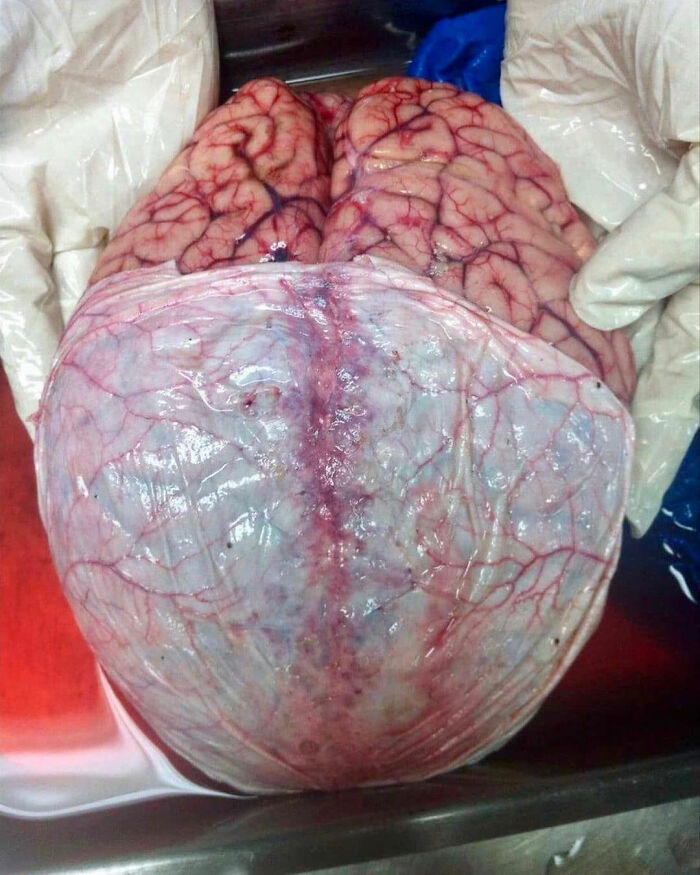

Here Is A Great Shot Showing The Brain With Its Covering Layer

Below the skull and around the spinel cord are three special coverings called the meninges. You may have heard of the illness called meningitis. Meningitis is an infection of the meninges.

The outer layer of the meninges is called the dura mater or just the dura. The dura is tough and thick andit can restrict the movement of the brain within the skull. This protects the brain from movements that may stretch and break brain blood vessels.

The middle layer of the meninges is called the arachnoid. Underneath the arachnoid is a space known as the sub-arachnoid space. It contains cerebrospinal fluid, which acts to cushion the brain.

Small projections of arachnoid mater into the dura (known as arachnoid granulations) allow CSF to re-enter the circulation via the dural venous sinuses.

The inner layer, the pia mater, is located underneath the sub-arachnoid space.It is very thin, and tightly adhered to the surface of the brain and spinal cord. It is the only covering to follow the contours of the brain (the gyri and fissures).

Like the dura mater, it is highly vascularised, with blood vessels perforating through the membrane to supply the underlying neural tissue.